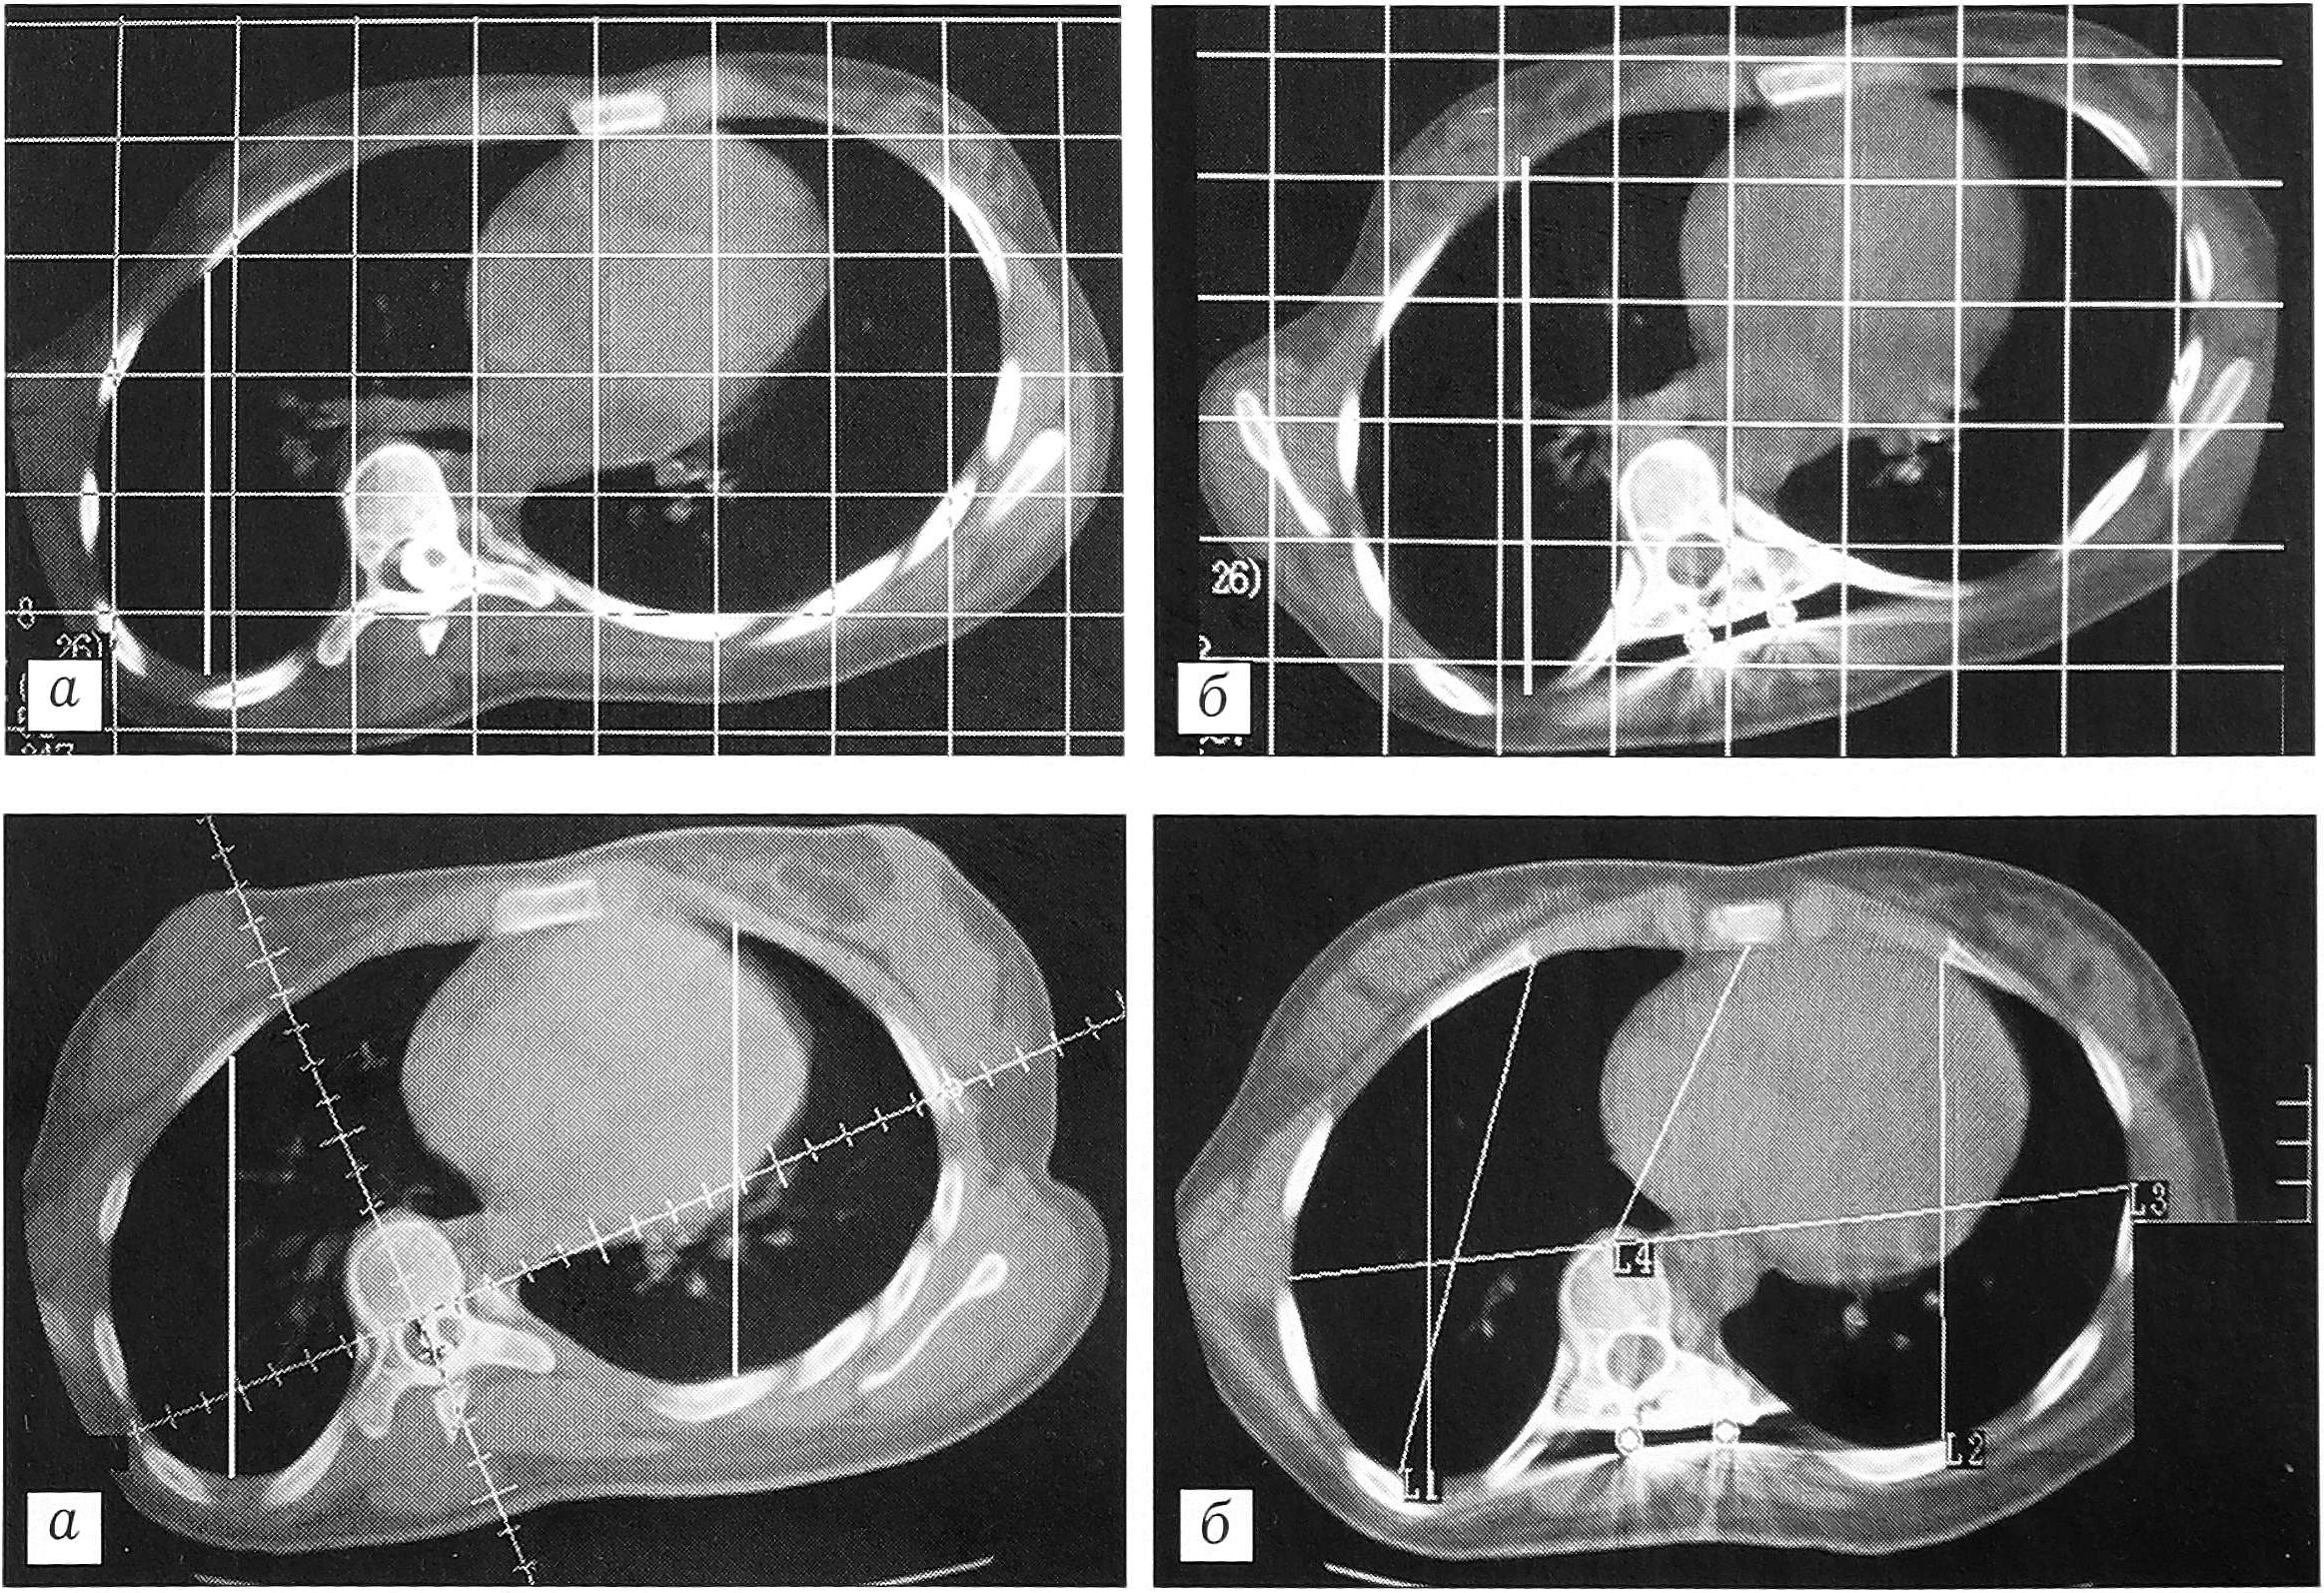

Рис. 1. Схема измерения ротации позвонка по методике Ааго и Dahlborn относительно передней срединной линии (а) и относительно сагиттальной плоскости (б).

Для объективизации результатов исследования и оценки степени изменений формы и размеров грудной клетки мы ввели и изучили 4 основных параметра (измерения проводили на уровне вершины деформации) (рис. 2): расстояние от внутренней поверхности грудины до передней поверхности тела позвонка (1); расстояние между наиболее удаленными точками боковых поверхностей грудной клетки в плоскости, максимально приближенной к фронтальной (2); расстояния от наиболее дорсальной точки грудной клетки справа и слева (вершина гиббуса) до наиболее вентральной точки с соответствующей стороны (3 и 4). При тяжелых деформациях мы дополнительно измеряли расстояния от боковой поверхности тела позвонка справа и слева до боковой поверхности грудной клетки с соответствующей стороны в сагиттальной плоскости (5).

Рис. 2. Основные параметры, используемые для определения размеров и формы грудной клетки у больных сколиозом (пояснения в тексте).

Расстояние между наиболее удаленными точками боковых поверхностей грудной клетки в плоскости, максимально приближенной к фронтальной, до операции равнялось в среднем 234,8±14,9 мм, после операции — 231,45±15,49 мм, т.е. уменьшилось на 3,35 мм (1,4% от исходного показателя), что укладывается в пределы ошибки метода. Максимальное уменьшение составило 12 мм, или 5,5% (рис. 7). Данный параметр уменьшился в послеоперационном периоде у 93% больных. Это изменение является следствием увеличения переднезаднего размера грудной клетки и отражает ее приближение к правильной овальной форме.

Рис. 7. Расстояние между наиболее удаленными точками боковых поверхностей грудной клетки до (а) и после (б) оперативного лечения (максимальное в исследуемой группе уменьшение данного параметра).

Расстояние от наиболее дорсальной точки грудной клетки до наиболее вентральной точки слева в послеоперационном периоде уменьшилось у 97% пациентов. До операции оно равнялось в среднем 121,6±8,22 мм, после оперативного лечения — 117,7±9,23 мм, т.е. разница составила около 4 мм (3,2% от исходного показателя). Однако есть примеры и достоверного изменения этого параметра — уменьшение на 11 мм, или 9,4%. Уменьшение расстояния от наиболее дорсальной точки грудной клетки слева до наиболее вентральной точки отражает стремление грудной клетки к симметрии.

Расстояние от наиболее дорсальной точки грудной клетки до наиболее вентральной точки справа до операции равнялось в среднем 120,9±12,1 мм. Минимальное расстояние составляло 99 мм; у этой же пациентки после оперативного лечения отмечено максимальное его увеличение — на 42 мм, или 42% от исходного показателя (рис. 8). После операции величина рассматриваемого параметра возросла в среднем до 127,3±7,19 мм, т.е. на 6,4 мм (5,3% от исходной). Увеличение расстояния от наиболее дорсальной точки грудной клетки справа (вогнутая сторона сколиотической деформации) до наиболее вентральной точки, отмеченное после оперативного лечения у 75,8% больных, отражает принятие грудной клеткой более правильной симметричной формы, а клинически проявляется уменьшением реберного горба.

Рис. 8. Расстояние от наиболее дорсальной до наиболее вентральной точки грудной клетки справа до (а) и после (б) оперативного лечения (максимальное в исследуемой группе увеличение данного параметра).

Таким образом, хотя выявленные изменения незначительны по величине, они имеют общую принципиальную направленность — приближение к правильной симметричной овальной форме грудной клетки в послеоперационном периоде. Максимально симметричной является грудная клетка с равными расстояниями от ее наиболее дорсальной до наиболее вентральной точки справа и слева (рис. 9).

Рис. 9. Восстановление симметричности грудной клетки после оперативного лечения (а — до, б — после операции).